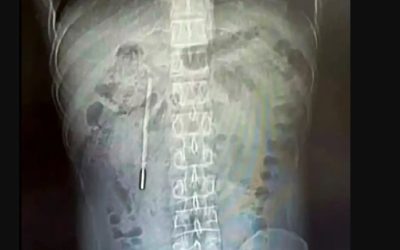

Un bărbat din China și-a descoperit cauza durerilor abdominale persistente: un termometru înghițit în copilărie, acum 20 de ani. Pacientul, identificat...